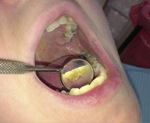

O ile stwierdzenie obecności kamienia naddziąsłowego (ryc. 1, 2) nie jest trudne, gdyż jest on widoczny w badaniu wizualnym i podczas zgłębnikowania, o tyle diagnostyka złogów poddziąsłowych może sprawić większy problem. Wzrokiem możemy ocenić tylko wysepki kamienia położone płytko, które uwidaczniamy za pomocą strumienia powietrza z dmuchawki unitu stomatologicznego. Zastosowanie lup oraz lepszego oświetlenia zwiększa czułość metody.[4] Jak podaje piśmiennictwo, w diagnostyce można wykorzystać sondę periodontologiczną. Cechuje się ona długą (10-12 mm) i odpowiednio zagiętą częścią pomiarową zakończoną kuleczką o średnicy 0,5 mm. Taka budowa zabezpiecza tkanki przyzębia przed traumatyzacją i umożliwia wyczucie nierówności na powierzchni korzenia.[5]